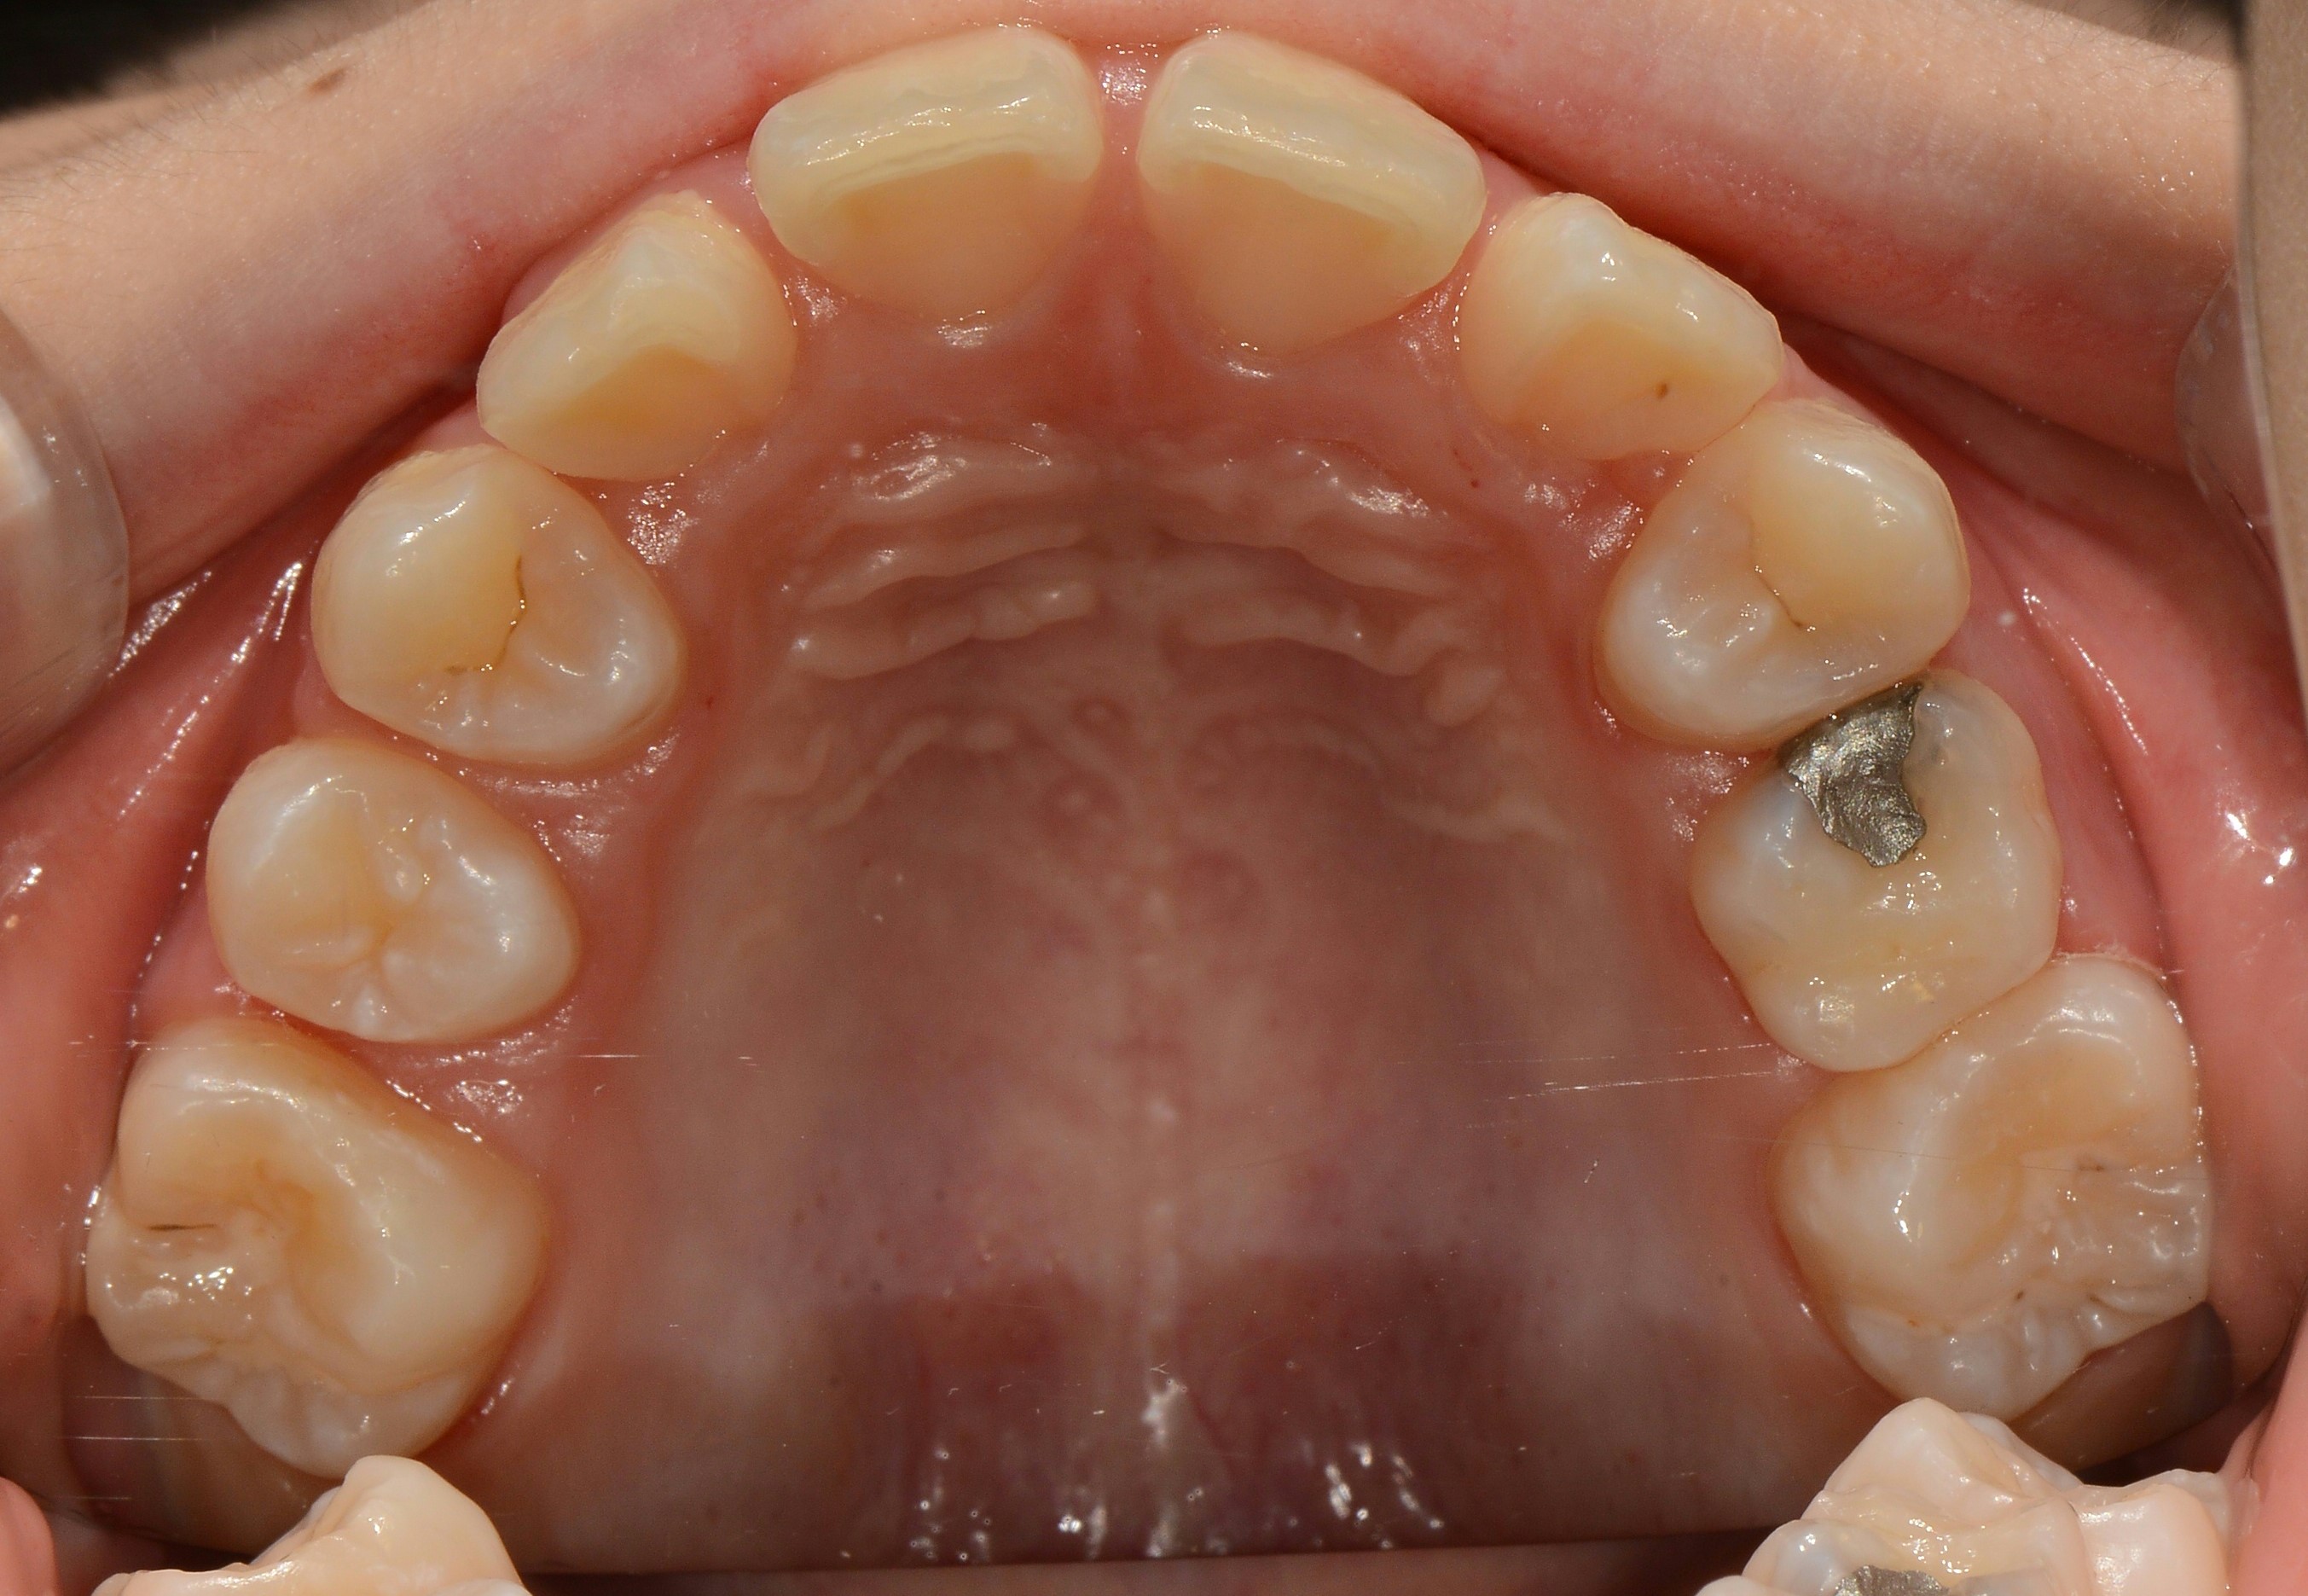

치료 후 사진입니다.